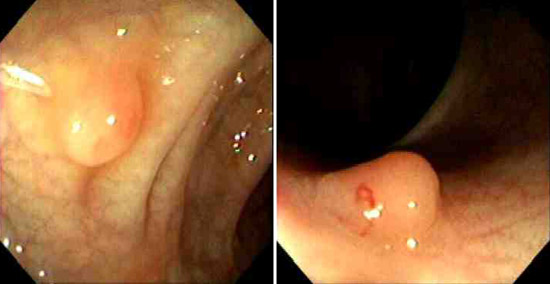

This small adenomatous polyp (tubular adenoma) on a small stalk is seen microscopically to have more crowded, disorganized glands than the normal underlying colonic mucosa. Goblet cells are less numerous and the cells lining the glands of the polyp have hyperchromatic nuclei. However, it is still well-differentiated and circumscribed, without invasion of the stalk, and is benign. Two colonoscopic views of a small polyp that proved to be a tubular adenoma is seen below. |